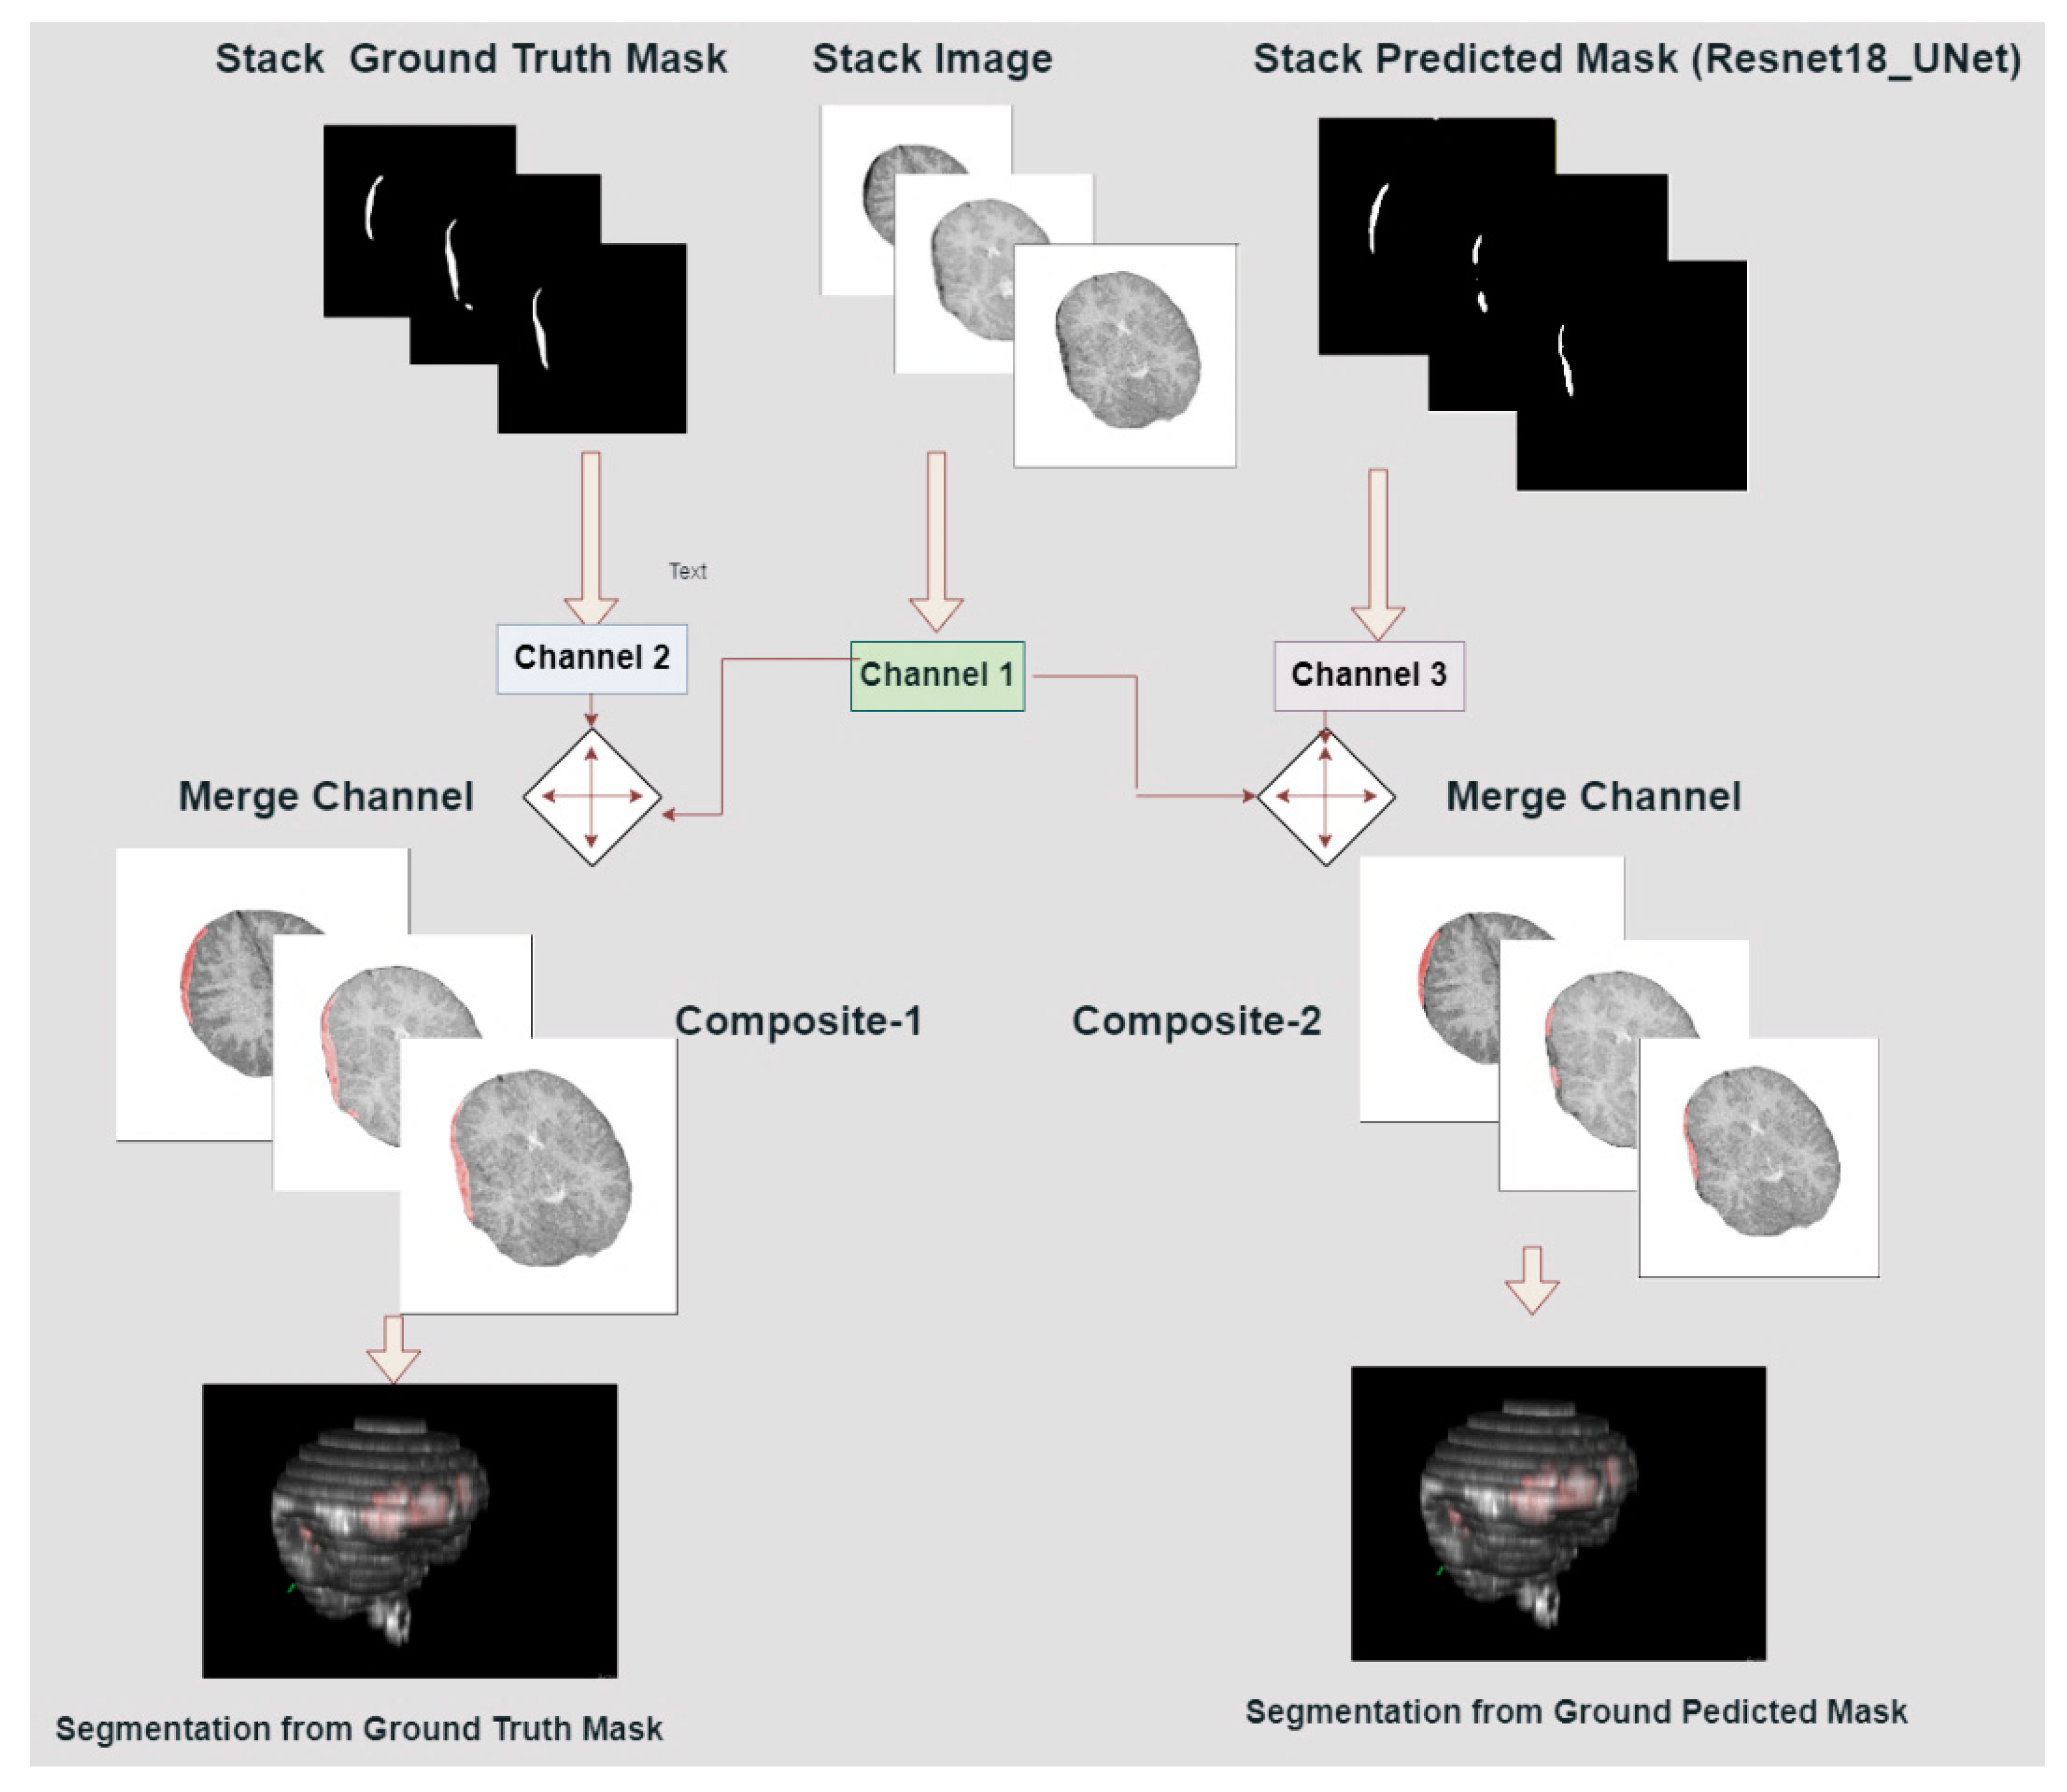

2.8. Volumetric Representation of ICH

2.10.2. 3D Construction of Brain and ICH